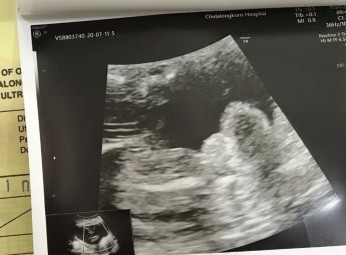

ได้ลูกสาวค่ะ😁

Post reply image